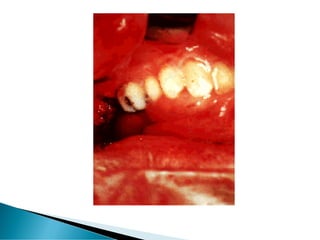

 Significant blood loss from a dental

procedure lasting more than 24 hours or

requiring blood transfusion.